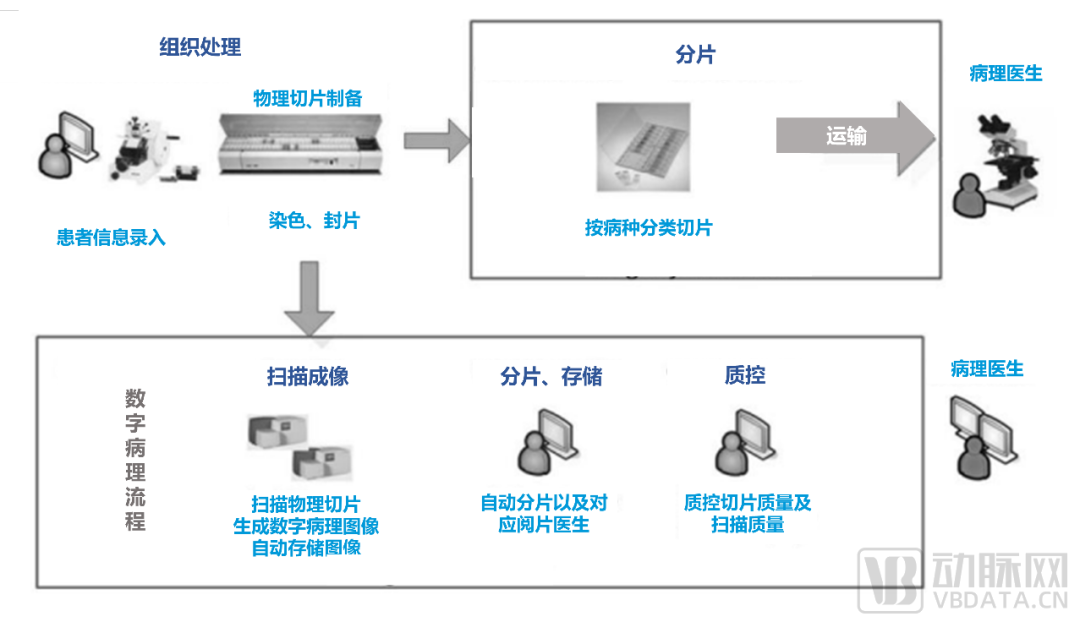

数字化病理科建设模块介绍

数字化建设模块图

来源:蛋壳研究院